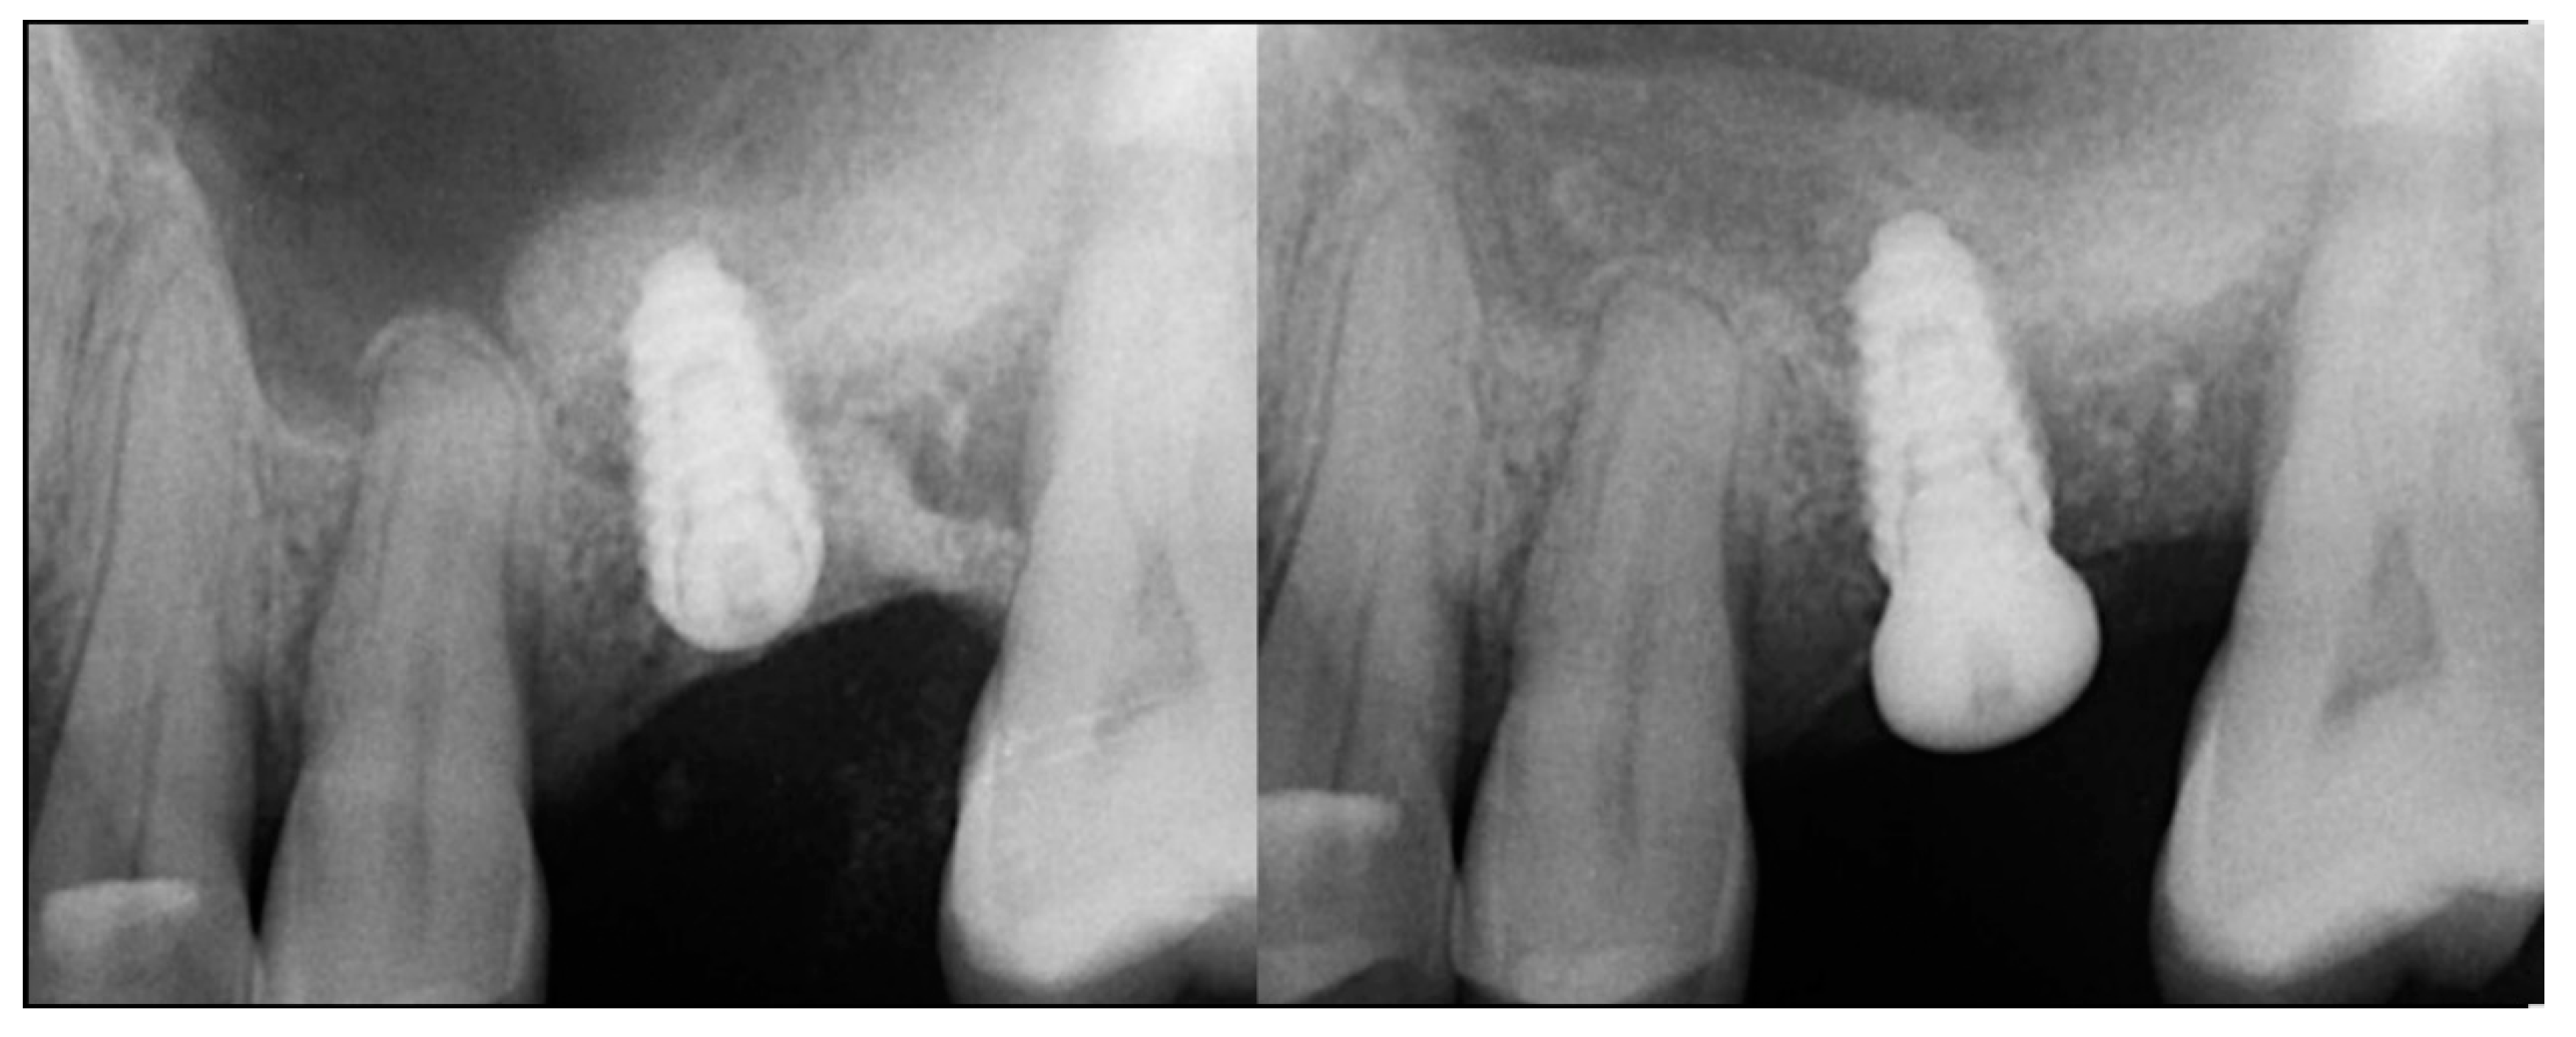

At 10 weeks post-extraction, the patient presented, and consent forms were reviewed and signed for grafting and implant treatment. Soft tissue had healed, closing the site with keratinized tissue (Figure 8, middle). A radiograph was obtained to check what available bone was present at both sites (Figure 8, right). Sufficient height was available to place an implant at the 1st molar site in conjunction with a crestal sinus augmentation, but insufficient height was present at the 2nd molar site which would require grafting to increase crestal height and later implant placement could be performed at that site.

Local anesthetic was administered, and a full thickness flap of the area was elevated. Utilizing a similar technique as outlined in case 1, the 1st molar site underwent a crestal lift and a 4.5 × 8.5 mm Anyridge (Megagen, Busan, Republic of Korea) implant was placed (Figure 9). The defect present at the 2nd molar site, resulted in a crestal height of 1.5 mm, which was insufficient for implant stability if a simultaneous crestal sinus left was performed (Figure 9, middle). Thus, grafting would need to be performed to prepare the site for later implant placement. EthOss graft material was hydrated in the syringe as previously described and placed into the defect to increase crestal height following healing (Figure 9, right).

Figure 9.

Site was reentered at 10 weeks post-extraction and an implant was placed with a crestal sinus augmentation utilizing EthOss graft material at the 1st molar site and a large defect was present at the 2nd molar site (left), with a radiograph obtained to document the implant placement at the 1st molar and grafting of the defect (middle) and following crestal grafting of the 2nd molar site (right). Green line is the measurement of the height of the bone at that point between the crest and the sinus floor.

The patient returned at 10-weeks implant and graft placement and the soft tissue over the posterior quadrant was noted to be healed with no inflammation present (Figure 10 left). Following local anesthetic administration a full thickness flap was elevated and the previously grafted 2nd molar crestal area was filled with immature host bone (Figure 10 right). A radiograph was obtained, which noted a crestal height of 7.1 mm present (Figure 11 left). The 2nd molar site was prepared in a similar fashion as previously detailed, utilizing Densah burs to osseodensify the area and accomplish a crestal sinus augmentation and a 5 × 8.5 mm Anyridge implant was placed (Figure 11 middle and right). An impression of the 1st molar implant was obtained to initiate its restoration while the 2nd molar implant was integrating. A healing abutment was placed on the implant at the 1st molar and a cover screw on the 2nd molar implant and a radiograph obtained to document the clinical result to date (Figure 12).

Figure 11.

Radiograph demonstrating sufficient height of the ridge to allow primary stability of an implant placed at the 2nd molar with a crestal sinus augmentation at 10 weeks of graft healing (left), site preparation for the crestal sinus augmentation (middle) and implant placement into the site (right). Green line is the measurement of the height of the bone at that point between the crest and the sinus floor.

Figure 12.

Radiograph following implant placement into the 2nd molar site with simultaneous crestal sinus augmentation.

The patient returned at 10 weeks post-2nd-implant placement and a screw-retained restoration was placed on the 1st molar and a radiograph was obtained (Figure 13, left). Impressions were obtained and the restoration on the 2nd molar was placed at a subsequent appointment. Soft tissue was healthy at placement of the restoration on the 2nd molar and no marginal inflammation was noted at either site (Figure 14, left). Soft tissue at the 1-year recall remained healthy and lacking in inflammation (Figure 14, middle). At a 2-year recall, a radiograph was obtained and bone was noted to be stable at both implants (Figure 13, right). Soft tissue at the 2-year recall remained stable and no change in marginal position was noted compared to initial restoration placement (Figure 14, right).

Figure 13.

Radiograph at 10 weeks implant integration at the 2nd molar (left) and two years following restoration of the implant at the 2nd molar showing the improved vertical regeneration between the implants (right).